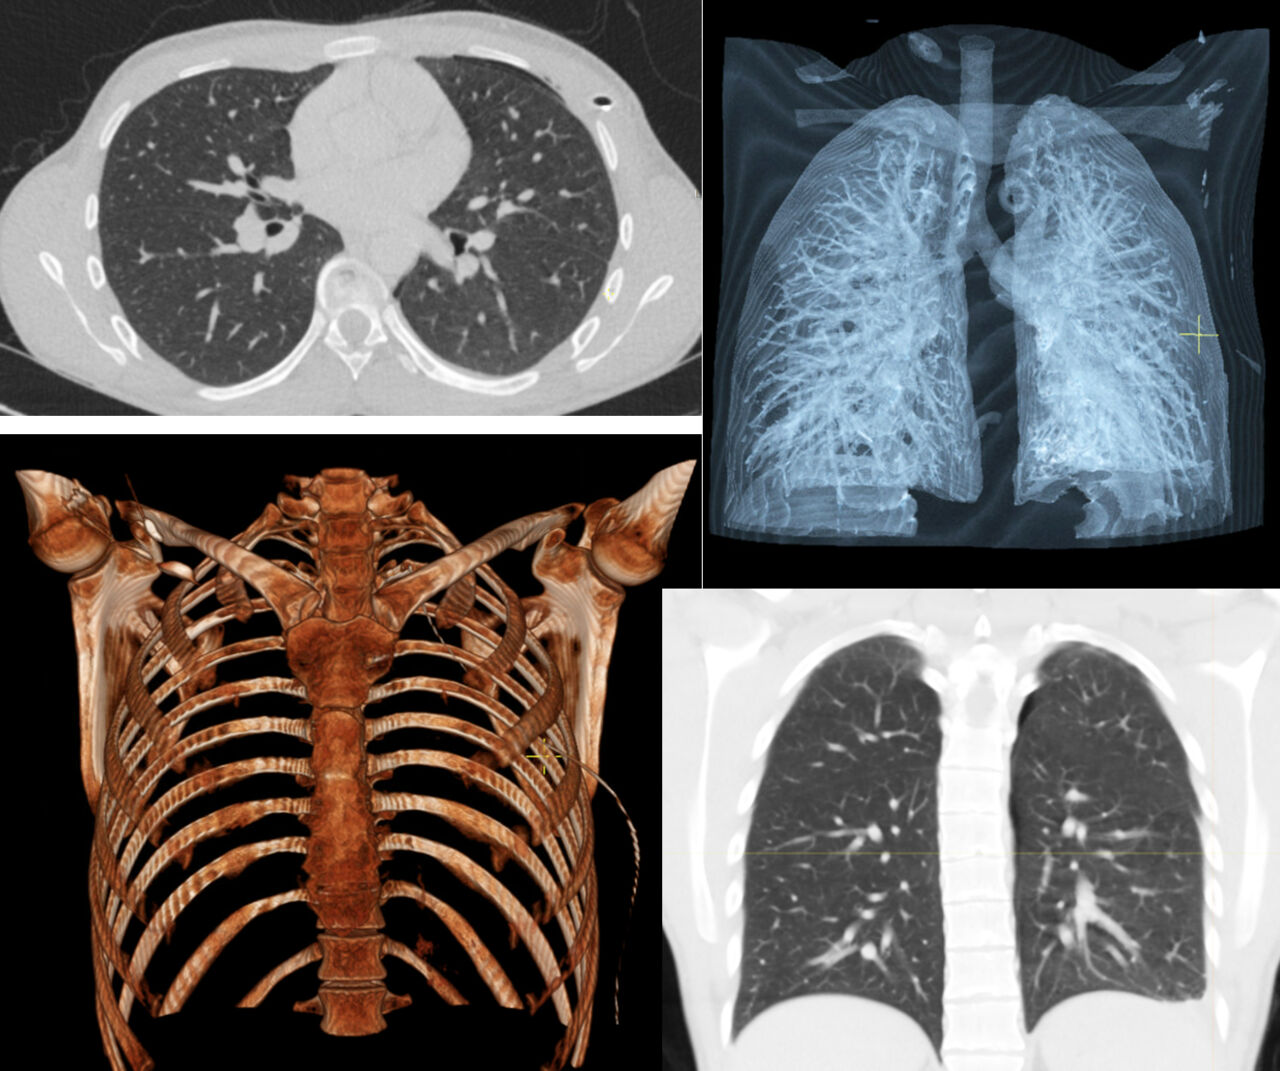

Röntgenbilder på lungor

CHALS är en substudie till SCAPIS2. I projektet används digitala stetoskop för att spela in hjärt- och lungljud på ett mer standardiserat sätt hos 5000 studiedeltagare i SCAPIS 2 i Linköping och Uppsala. Det digitala stetoskopet är kopplat till en mobilapplikation och de inspelade hjärt- och lungljuden kommer att analyseras i förhållande till fynd vid skiktröntgen av hjärtat och lungorna, ultraljud av hjärtat och lungfunktionsundersökning med spirometri.

I CHALS kommer vi jämföra olika mönster av hjärtljud i relation till fynd vid hjärtultraljud (EKO) och datortomografi av kranskärl. Det datortomografin som används är den allra modernaste (Fotonräknande datortomografi) och har en mycket hög upplösning.